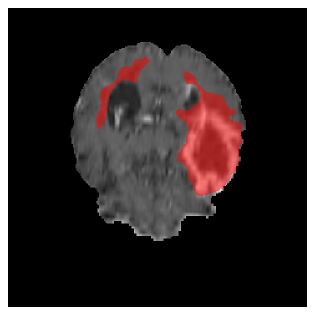

Appendix A Qualitative results

Figures 4 and 5 present the segmentation results for a patient from the BRATS dataset, visualized on a randomly selected slice. Figure 4 illustrates how tumor segmentation evolves over multiple episodes in S1 across different approaches including cumulative, naive, our approach, and the best buffer-free strategy (SI, =2). The cumulative approach, which trains on all encountered datasets together, maintains segmentation consistency across episodes but introduces significant amounts of false positives, particularly in the upper left area of the brain images. These misclassifications highlight its inability to generalize well across datasets despite access to all previous data. The naive approach, which learns sequentially without any continual learning strategy, suffers from severe catastrophic forgetting. While it initially segments well, performance deteriorates over episodes, leading to a near-complete loss of segmentation capability by the final episode. The SI (=2) approach, a regularization-based buffer-free CL strategy, performs reasonably well in early episodes but shows a significant performance decline over time. By the last episode, much of the tumor was no longer segmented, indicating difficulty in retaining prior knowledge. In contrast, our proposed approach initially produces more false positives but progressively refines its segmentation. By the final episode, it accurately retains the tumor region while minimizing misclassifications, demonstrating strong knowledge retention and adaptability across episodes. This suggests that our approach effectively mitigates catastrophic forgetting while maintaining segmentation performance over sequential learning.